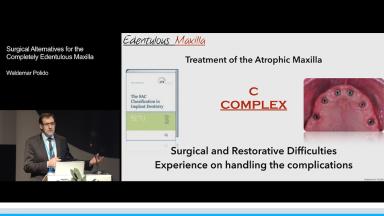

Surgical Alternatives for the Completely Edentulous Maxilla

Rehabilitation of the edentulous maxilla is always a complex task that requires a comprehensive treatment plan. Patients desire implant-supported prostheses with minimal future complications. With this in mind the treatment plan must start with an evaluation of patient expectations, with the definite prosthesis as the starting point as well as the final goal. Patients should be presented with the risks of different surgical approaches as well as the required maintenance procedures for different rehabilitations so that these factors are included in the decision-making process. This lecture addresses all of the aforementioned points, leaving the viewer with a clear “big picture” for full-arch maxillary reconstructions.

- explain the challenges in rehabilitating the edentulous maxilla